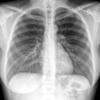

Normal PA

24 yo male

Date: 06/08/2016

Views: 6132